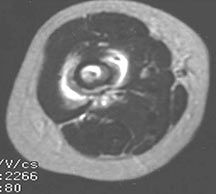

- May arise from any bone and any site within a bone (epiphyseal, metaphyseal, diaphyseal)

- Radiographically variable appearance: may appear benign (geographic) or malignant (permeative or moth eaten)

- Femur